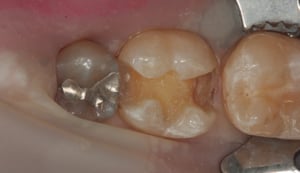

Otturazione in composito a livello di primo molare inferiore destro. Il restauro in amalgama di argento esistente presenta una frattura e viene pertanto sostituito. La rimozione del materiale metallico viene eseguita isolando il dente dal cavo orale mediante diga di gomma. Il dente viene come per ogni procedura sabbiato, mordenzato, trattato con primer ed adesivi ed infine otturato in materiale composito fotopolimerizzabile. La presenza di cuspidi intatte e di spessore sufficiente, conferisce una adeguata resistenza meccanica al restauro eseguito.